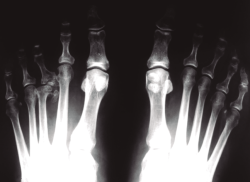

Figura 6. Tratamiento quirúrgico. La resección aislada de la cabeza suele dar malos resultados.

- Resección de la cabeza del metatarsiano. Esta técnica clásica propuesta por algunos autores(18,19,20) elimina el dolor articular pero tiene el grave inconveniente de que provoca una importante desalineación del antepié con la correspondiente metatarsalgia de transferencia (Figura 6).